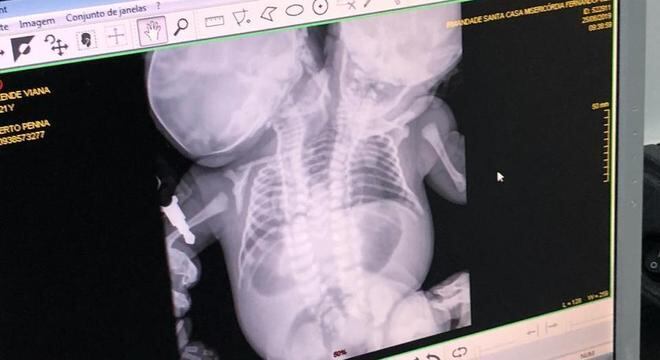

Elas nasceram ligadas pelo tronco, mas possuem 4 pulmões, dois corações e duas colunas vertebrais distintas. Elas estão internadas na UTI do Hospital da Criança de São José do Rio Preto, para onde foram transferidas da Santa Casa de Fernandópolis logo após o parto.